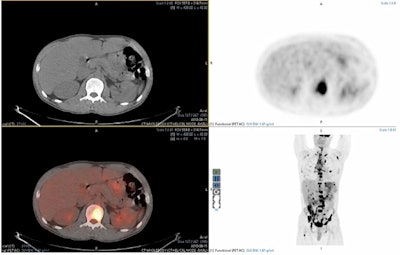

Image demonstrating the viewing panel from Mirada XD. Image courtesy of Dr. Andrew Scarsbrook.Overall, there was a significant decrease in time between non-AI and the AI-assisted reads (a median of 15 minutes versus 13.3 minutes, according to the findings. A subanalysis by reporter experience showed that this held true for junior (14.5 minutes versus 12.7 minutes, p = 0.03) and senior consultants (15.1 minutes versus 12.2 minutes, p = 0.03), although no significant improvement was seen in trainees.